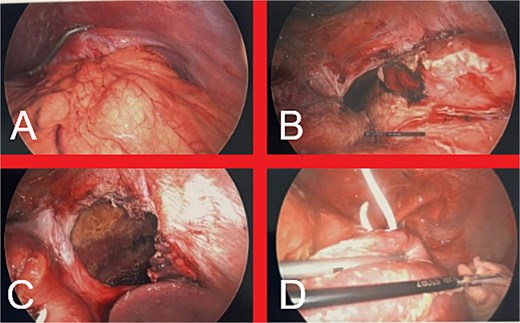

We proceeded with emergent surgical intervention the same day (Fig. 5). Using an entirely laparoscopic approach, the hernia sac was painstakingly mobilized, with extension of the diaphragmatic defect being necessary to reduce the stomach into the abdominal cavity. A 3 cm gastric fundus perforation was identified and definitively controlled with a stapled partial fundectomy. The thoracic and abdominal cavities were thoroughly irrigated, followed by insertion of two ICCs and two abdominal drains for ongoing contamination control. The DH defect was repaired primarily with a nonabsorbable suture and reinforced with an absorbable synthetic mesh. Gastroscopy confirmed viable gastric mucosa and facilitated NGT and nasojejunal tube (NJT) insertion. She was transferred to the Intensive Care Unit postoperatively and received broad-spectrum intravenous antibiotics (piperacillin-tazobactam and fluconazole) for presumed mediastinitis.

(A) Intraabdominal view of the DH upon initial laparoscopic entry into the abdomen. (B) Appearance of the stomach following dissection of the hernia sac and reduction of the stomach into the abdominal cavity, revealing a 3 cm perforation in the gastric fundus. (C) Final appearance of the large diaphragmatic defect prior to definitive repair. (D) Intrathoracic view of left hemithorax, demonstrating contamination with gastric contents, fibrin deposition on the left lung and the previously inserted ICC.